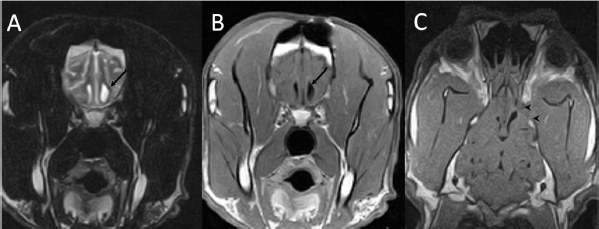

A 3-year-old female Great Dane was referred for acute onset behavioral changes (aggression and disorientation) of 2 weeks duration, and seizures from 24 hours prior to presentation. Physical examination revealed no abnormalities in body temperature, body condition score, heart rate, pulse quality, or cardiopulmonary auscultation. All lymph nodes were considered of normal size and no pain was elicited upon manipulation of the orbital, aural, or cranial musculature. Neither was there any history of dermatological or traumatic lesions in the eye, ear, or mouth. The neurological examination revealed the patient to be obtunded with decreased postural reactions and menace response worse in the left side. Neuroanatomic lesion localization was considered focal in the right prosencephalon with a possible increase in intracranial pressure. Hematological and serum biochemical analysis showed no abnormalities. Magnetic resonance imaging was performed using a low-field magnet (Airis Mate; Hitachi, Tokio, Japan). The study revealed a left-sided single frontal intra-axial lesion affecting gray and white matter adjacent to the internal capsule at the level of the optic canal (Fig. 1). The lesion presented signal homogeneity characterized by hyperintensity on T2W and FLAIR sequences and hypointensity in T1W sequences with peripheral enhancement after intravenous contrast administration (Fig. 1A and 1B). The lesion had a round shape with the greatest diameter of 2.84 cm. This enhancement was also recognized in the surrounding meninges following the brain surface following sulci. A small linear tract observed was directed dorsally from the lesion through the corona radiata (Fig. 1B). The lesion was associated with extensive perilesional vasogenic edema that worsened the mass effect characterized by a midline shift. The orbital and medial pterygoid muscles also showed an intense enhancement (Fig. 2). The wing of the presphenoid bone was thinner than the contralateral bone (Fig. 1B). A CT scan (Astelion 16, Toshiba, Tokio, Japan) was performed after MRI that allowed the identification of osteolysis in the presphenoid bone immediately dorsal to the orbital fissure (Fig. 1C). CT scan also revealed a hypoattenuating intra-axial lesion located in the left frontoparietal lobe together with diffuse hypoattenuation of tissues adjacent to the left optic nerve and the left pterygoid muscle. Finally, CSF analysis showed no abnormalities. On the basis of advanced radiological findings, the main differential diagnosis was an intracranial abscess due to the extension of the extracranial septic process through presphenoid bone. Because of rapid neurologic deterioration and suspected increased intracranial pressure, surgical excision was planned. A modified left rostrotentorial craniectomy was performed. Temporalis muscle and fascia were retracted, extending the incision cranially through the temporal line. Once the frontal and presphenoid bones were exposed an area of osteolysis was observed in the wing of the presphenoid bone immediately dorsal to the orbital fissure. The craniectomy (approximately 3 cm diameter) was centered on the osseous defect. A mucopurulent discharge presented immediately after the incision of the dura mater. A sample was collected for its microbiological study. The surgical site was flushed with sterile saline revealing the tip of a grass awn which was extracted from the brain parenchyma together with a small amount of purulent fluid (Fig. 3). After extensive flushing, the meninges were left open to allow drainage and the incision was closed as per routinely. Postoperative CT showed the correct location of the craniectomy and resolution of the abscess which was substituted by gaseous content but remained inside and on the dorsal surface of the frontal lobe (Fig. 4). Immediate postoperative therapy consisted of amoxicillin + clavulanic acid (Synulox 500, Zoetis Spain SL) 22 mg/kg PO, q8h; marbofloxacin (Marbocyl P80, Vetoquinol SA) 5 mg/kg PO, q24h; metronidazole (Flagyl 250, Sanofi-aventis SA) 15 mg/kg PO, q12h; prednisone (Prednisona Kern Pharma 30mg, Kern Pharma) 0.5 mg/kg PO, q12h; tramadol (Tramadol retard Combix 100 mg, Laboratorios Combix S.L.U) 2 mg/kg PO, q8h; famotidine (Famotidina Normon 40 mg; Laboratorios Normon SA) 0.7 mg/kg PO, q24h; and phenobarbital (Phenoleptil 100 mg, Le Vet BV) 2.5 mg/kg PO, q12h. Cultured samples were positive for Pseudomonas aeruginosa sensitive to ciprofloxacin, imipenem, and amikacin among other antibiotics. Based on these results, antibiotic therapy was changed to ciprofloxacin (Ciprofloxacino 500, Laboratorios Normon SA) 10 mg/kg PO, q12h and metronidazole 15 mg/kg PO, q12h for 2 months. Prednisone, tramadol, and famotidine were withdrawn and phenobarbital was maintained at 2.5 mg/kg q12h. Six-month post-operative revision magnetic resonance revealed no signs suggesting the existence of an inflammatory process (Fig. 5). In the area where the abscess had been located, a fluid-filled cavity suggesting being CSF was observed. One year follow-up revealed the patient had seizures every 3 months with neurological examination remaining normal. The patient died 2 years later of unrelated causes.

Fig. 1. (A) Transverse T2-weighted image, (B) transverse post-contrast T1-weighted image, and (C) transverse CT image obtained at the level of the optic canal (asterisk). The lesion can be seen as a hyperintense (arrow in A) and ring-enhancing mass (arrow in B) located in the left frontal lobe. Note thinning of the wing of the presphenoid bone (arrowheads in B and C).

Fig. 2. (A) Transverse and (B) dorsal post-contrast T1-weighted images revealing enhancement of orbital musculature and medial pterygoid muscle (arrows).